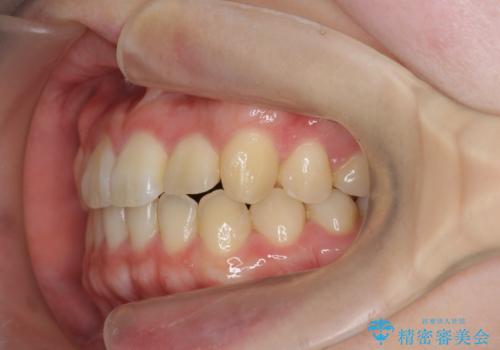

マススピース矯正を始める前に、部分ワイヤー矯正を行うことで治療の短期間化・良好な仕上がりを達成することができました。

- 1年3ヶ月

インビザラインの不得意な上顎前歯のねじれの改善を、マウスピース矯正を行う前に前歯のみの部分ワイヤー矯正を行うことで治療期間の短期化を目指します。